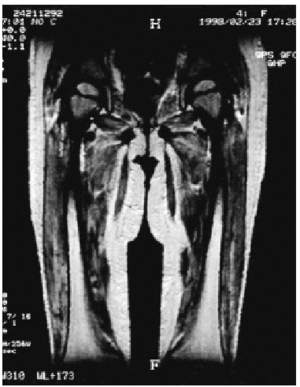

Se realizaron radiografías simples de miembros superiores y de miembros inferiores, que fueron normales. La RM de las piernas mostró aumento de señal en las secuencias T2 en los músculos del compartimiento posterior de ambas piernas (fig. 2). La RM a nivel de los muslos mostró aumento importante de señal en T2 de prácticamente todos los músculos anteriores y de casi todos los músculos posteriores (fig. 3). En la piel se apreció engrosamiento con zonas hipointensas en T1 e hiperintensa en T2. No se identificaron calcificaciones.

Fig. 2.--RM de piernas. Aumento de la señal en las secuencias T2 en los músculos del compartimiento posterior de ambas piernas.

Fig. 3.--RM de muslos. Aumento importante de señal en T2 en prácticamente todos los músculos anteriores y de casi todos los músculos posteriores.

Keim et al2 describieron los hallazgos en las RM seriadas de los pacientes afectados por esta enfermedad entre el momento del diagnóstico y 16 meses después de haberse iniciado el tratamiento con prednisona y observaron que los músculos afectados mostraban aumento en la intensidad de la señal en T2 y la secuencia T1 normal, retornando las imágenes a la normalidad con el tratamiento. Este aumento en la intensidad de la señal en la dermatomiositis juvenil se cree es secundario al aumento de agua extracelular2.

Hernández et al3 estudiaron 24 niños (19 con dermatomiositis y cinco sanos como control) y realizaron un total de 44 RM. Todos los pacientes con enfermedad clínicamente activa tenían alteraciones en la RM, mientras que aquellos con enfermedad inactiva y los controles tenían hallazgos normales en la RM. Los músculos afectados tenían aumento de la intensidad de la señal en T2 y aspecto normal en T1.

Los hallazgos de dermatomiositis juvenil activa en RM en T2 incluyen aumento de la intensidad de la señal en el músculo afectado (intrafascial), edema perimuscular (interfascial) y aumento de la intensidad de la señal en la grasa subcutánea. En estadios precoces de la enfermedad, el hallazgo más prominente es el edema del tejido subcutáneo y músculo. Después del tratamiento, la intensidad de la señal del músculo retorna a la normalidad. El edema muscular puede comenzar a resolverse, incluso a la semana de comenzado el tratamiento. En general, los músculos menos afectados retornan a la normalidad antes que aquellos que se encuentran gravemente afectados. En estadios tardíos se produce una disminución del volumen muscular, contracturas articulares, cambios óseos secundarios y calcificación de tejidos blandos.